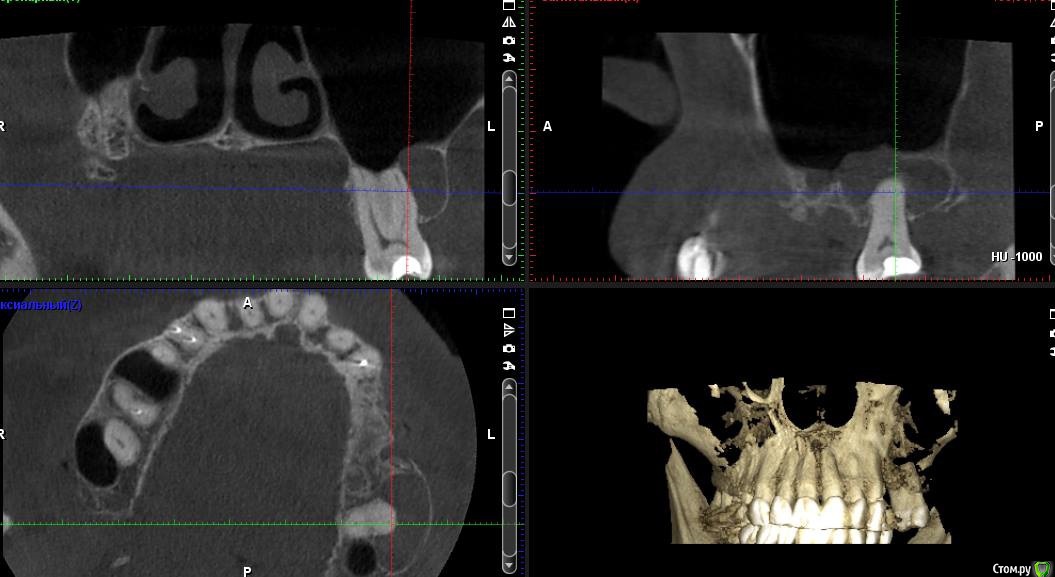

togrul Опубликовано 6 апреля, 2017 Поделиться Опубликовано 6 апреля, 2017 (изменено) Добрый день коллеги . Необходима Ваша помощь в планировании лечения. Пациентке нужно установить 2 имплантата в позиции 24-26. При анализе кт пришёл к выводу : 1 - провести НКР для восстановления высоты сеткой , через 6 месяцев установка имплантатов . 2- в области 27 зуба есть радикулярная киста , как вы считаете ее нужно убирать или нет и радикулярная ли данная киста? 3 - нужно ли проводить синус с нкр или лучше провести после НКР закрытый синус ? Буду благодарен за ответы.IMG_3292.BMPIMG_3293.BMPIMG_3294.BMP Изменено 6 апреля, 2017 пользователем togrul Ссылка на комментарий

Хью Крейн Опубликовано 6 апреля, 2017 Поделиться Опубликовано 6 апреля, 2017 Киста есть. Убирать лучше с зубом. Т.к. эндолечение вряд ли будет эффективно.Вестибулярно у зуба кости очень мало. Между кистой и верхнечелюстным синусом костная стенка есть. Синус лучше открытый,вместе с НКР. И ждать от 6 месяцев.Я бы сделал так. Ссылка на комментарий

togrul Опубликовано 6 апреля, 2017 Автор Поделиться Опубликовано 6 апреля, 2017 Спасибо за комментарий. Просматривая кт зуб 27 не вовлечен в полость кисты. Я завтра скину срезы другии, Но слизистая шнайдеровой мембраны сращена на мой взгляд с кистой . И еще один момент это рубец на границе неподвижной слизистой к подвижной. Ссылка на комментарий

togrul Опубликовано 29 августа, 2017 Автор Поделиться Опубликовано 29 августа, 2017 (изменено) Убрал содержимое кисты , получил мутное содержимое +убрал эпителий . Было сообщение полости с синусом . Ждал 3 месяца . Вот результат. Изменено 29 августа, 2017 пользователем togrul Ссылка на комментарий

CToMaToJlor Опубликовано 30 августа, 2017 Поделиться Опубликовано 30 августа, 2017 а полостное образование к 7 точно имело отношение? а то по представленным срезам мне это не показалось очевидым 1 Ссылка на комментарий

togrul Опубликовано 31 августа, 2017 Автор Поделиться Опубликовано 31 августа, 2017 (изменено) а полостное образование к 7 точно имело отношение? а то по представленным срезам мне это не показалось очевидымНет не имело. но проведя холодовой тест, зуб не реагировал. было принято решение его депульпировать. И вовремя лечения терапевт отметил, что пульпа практически была некротизирована. Изменено 31 августа, 2017 пользователем togrul Ссылка на комментарий